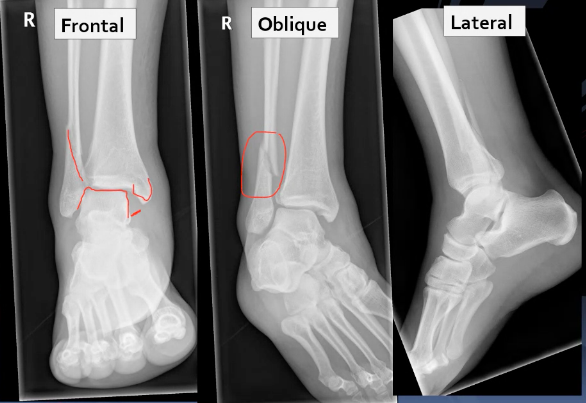

A 25 year old man presented to the ED with right ankle pain after a fall.

He was struggling to walk. His ankle was swollen and tender on examination. Movement was limited due to pain.

What can you see? What injuries are present?

A 30 year old woman presented to the ED with right ankle pain after a fall. She was struggling to walk. Her ankle was swollen and tender on examination. Movement was limited due to pain.